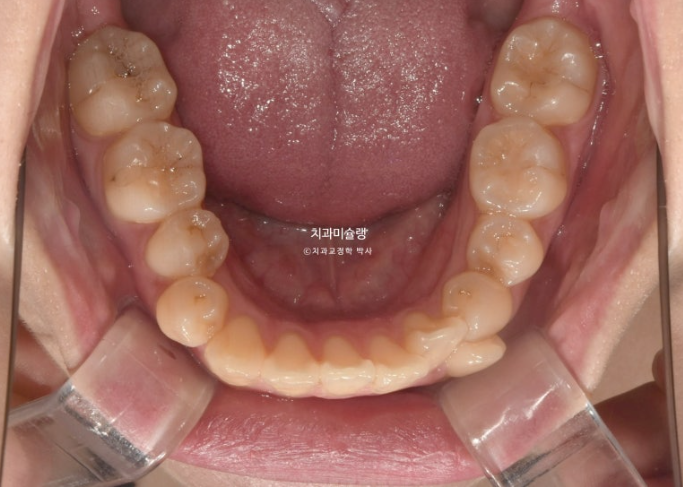

23년 10월 교정치료를 이해 온 30대 환자분입니다.

약 2mm 정도의 중심선 불일치 그리고 덧니가 보입니다.

개방교합도 있고

30년간 공간이 없어서 미처 내려오지 못한 작은어금니도 있습니다.

덧니가 워낙 심해 작은어금니 4개 발치가 불가피한 상황입니다.